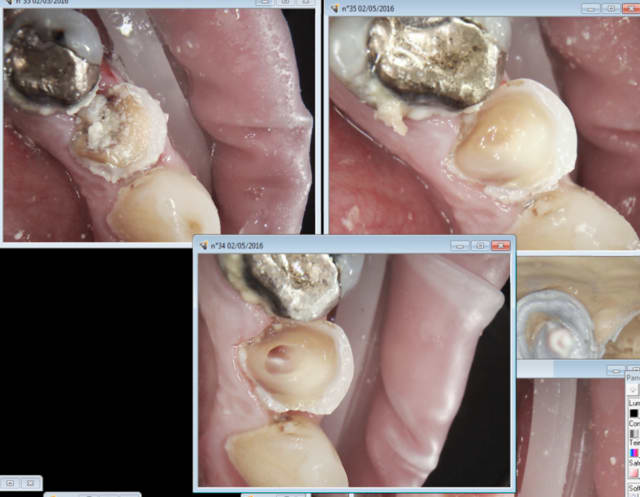

02/05/2016 à 21h55

Il faut s'adapter à notre nomenclature de merde sans pour autant en faire. -)

Endo, taille, empreinte, provisoire : 40 mn. Durée de RDV : 1H donc 20 mn pour se détendre et ré attaquer de plus belle le patient suivant. -) -)

J'ai merdé quelque part : devinez ou ? -)

30 mn de plus pour RTE taille de la 5. Pfffff taux horaire de merde ! -)))

Sinon enlaye j'essaie de faire un effort pour les limites de préparation. -))